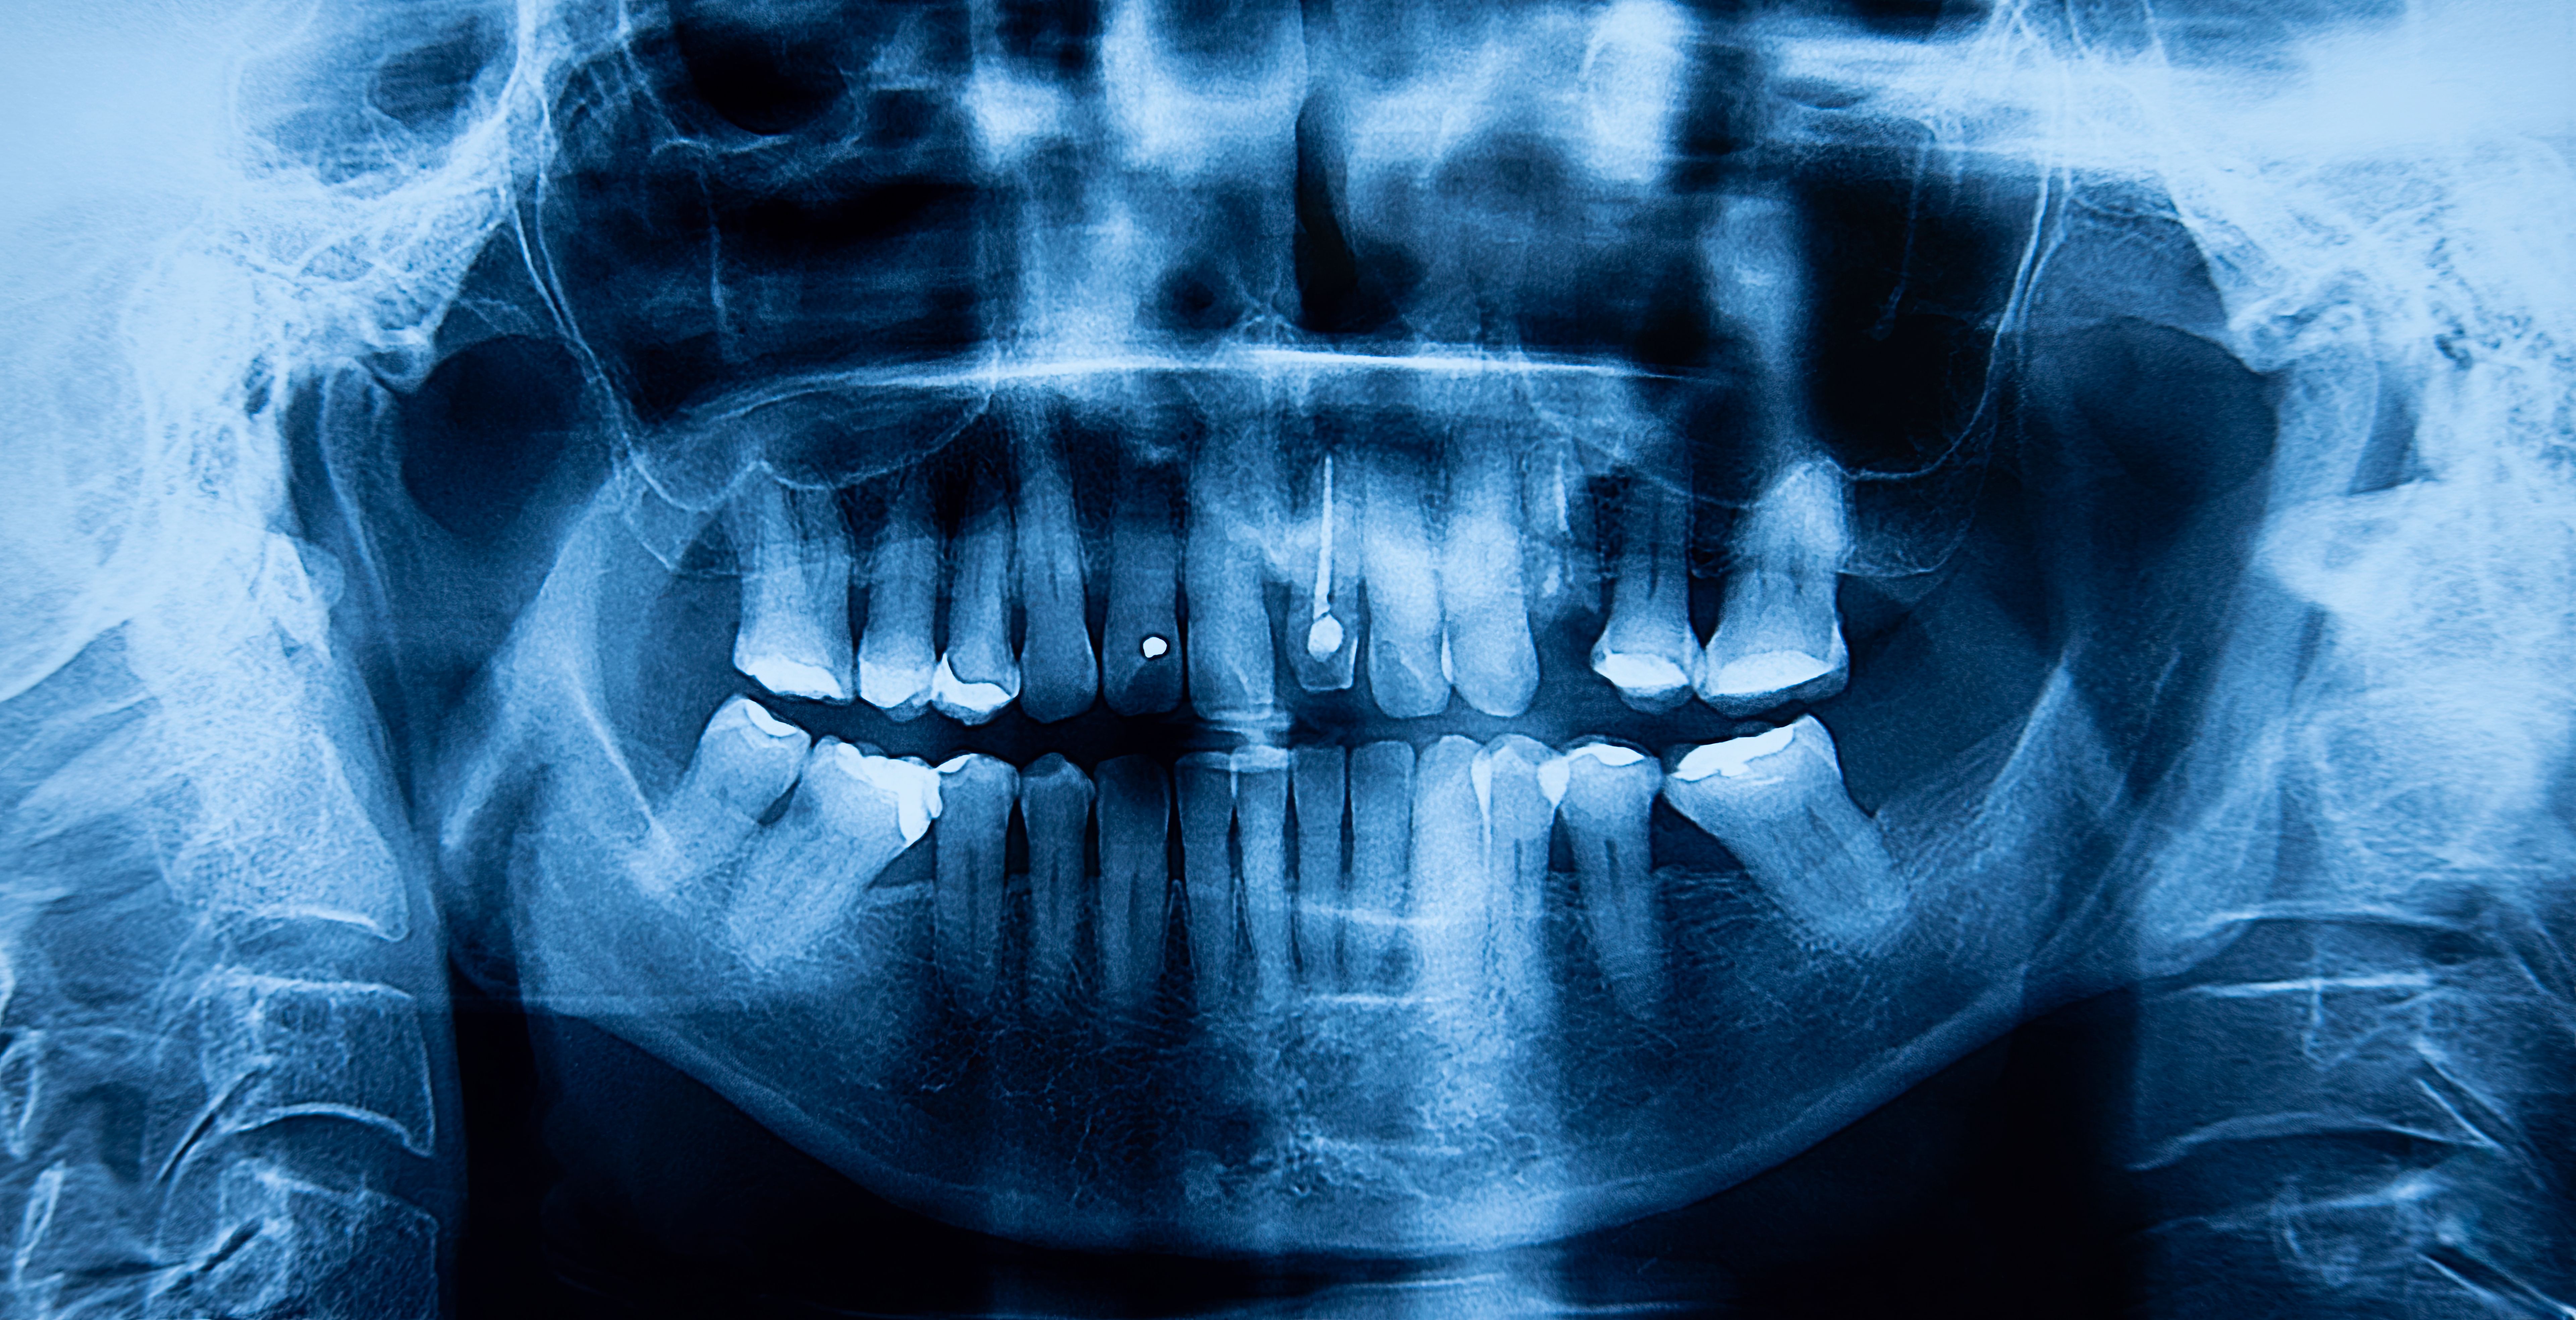

In the medical field, imaging technology plays a crucial role in diagnosing and treating patients. Among the various imaging tools available, X-ray systems are indispensable for visualizing internal structures of the body. However, not all X-ray systems are stationary; some are designed for mobility. Understanding the difference between portable and mobile X-ray systems can help medical professionals select the most appropriate tool for their needs.